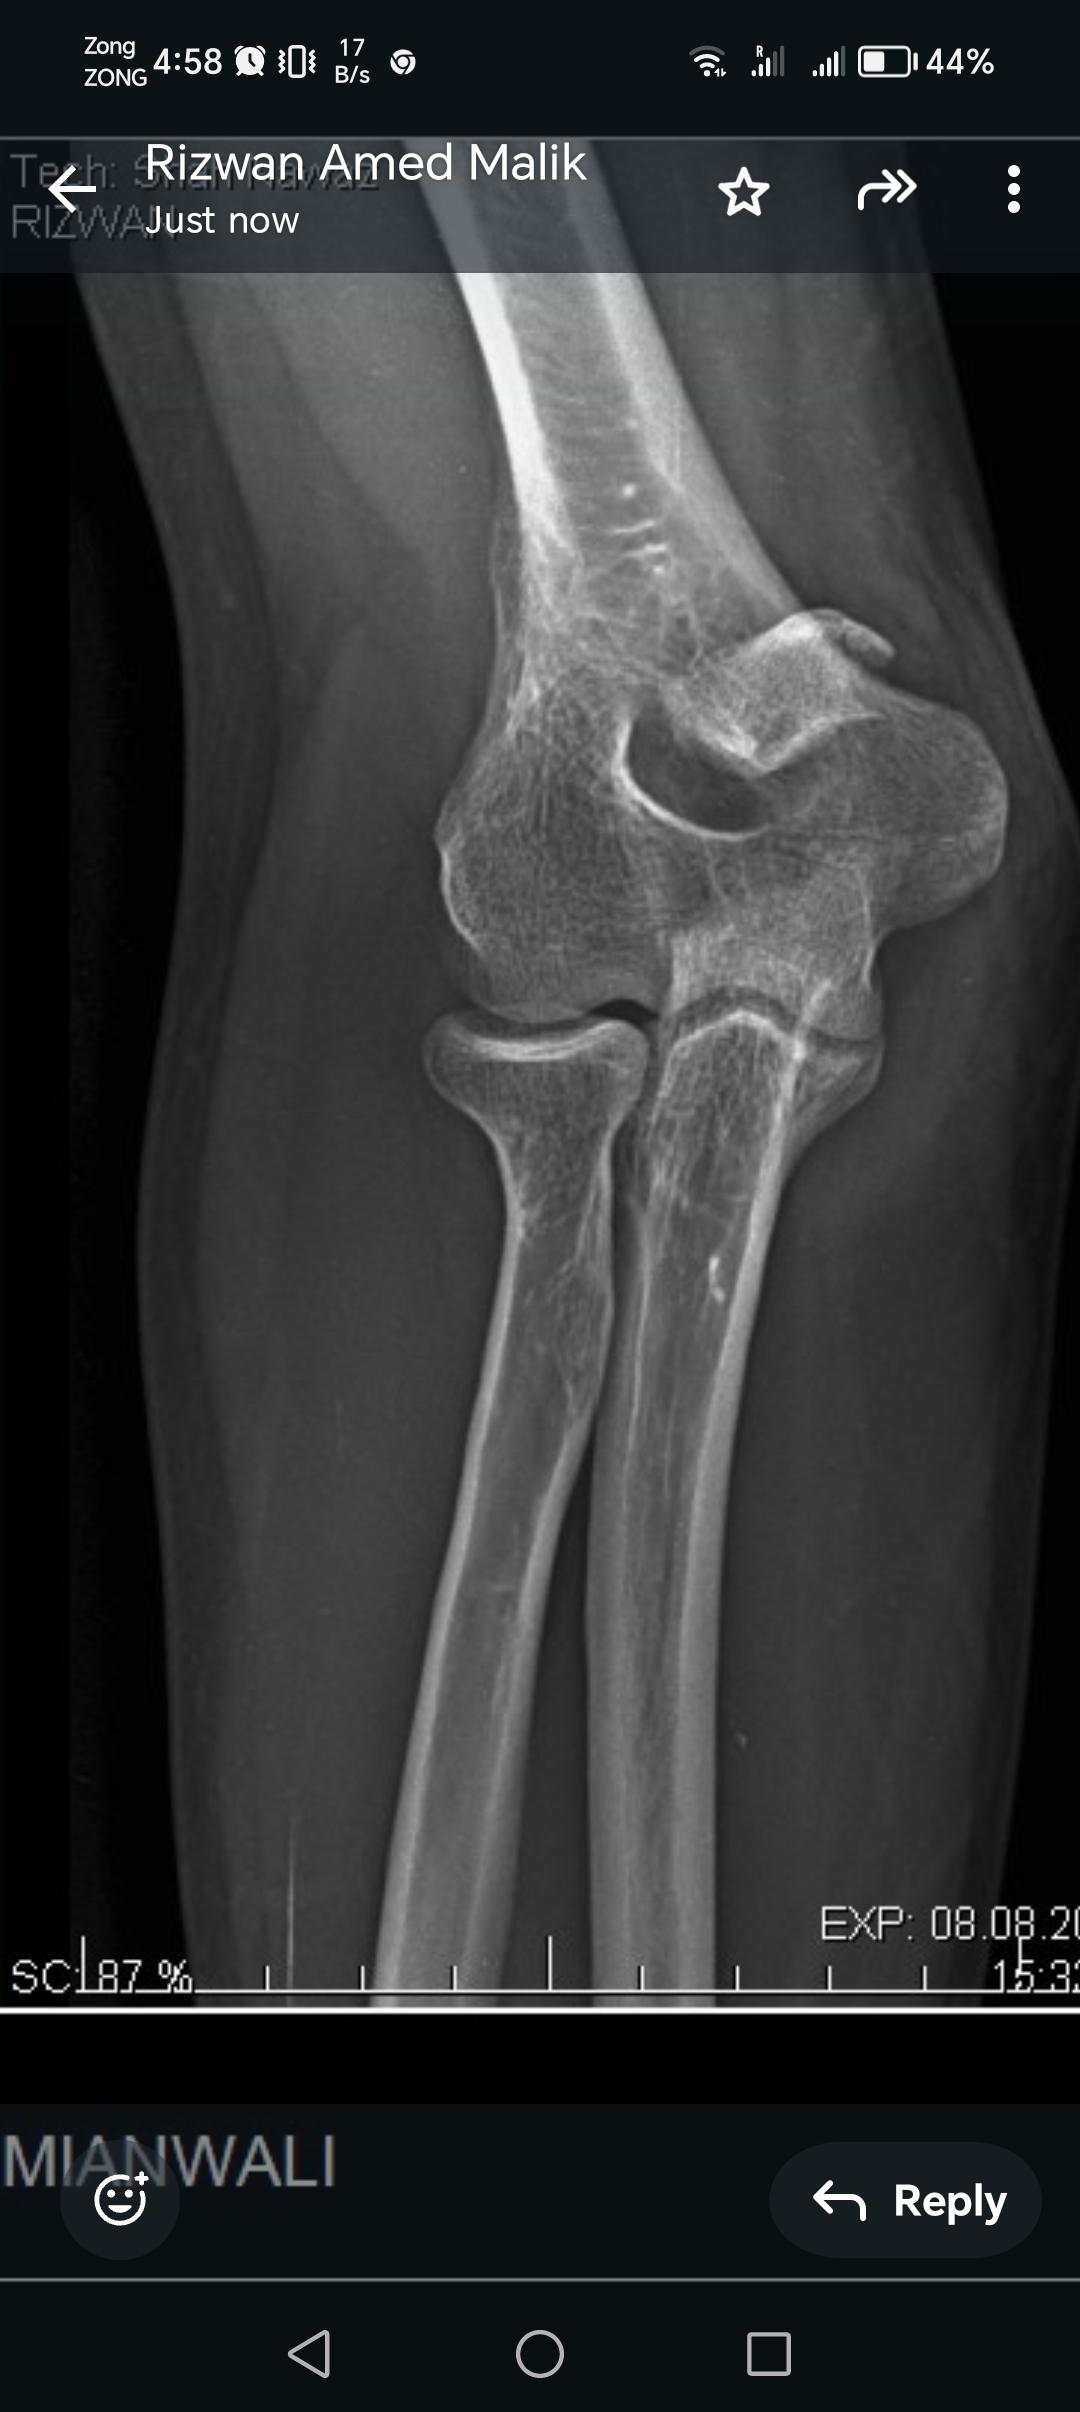

My husband had elbow surgery on 9th of August. I want to know about physiotherapy. When can we start physiotherapy so he can bend and extend his arm freely.Kindly guide us. If we start now will it effect joint or not. TIA

Attach Photo here: